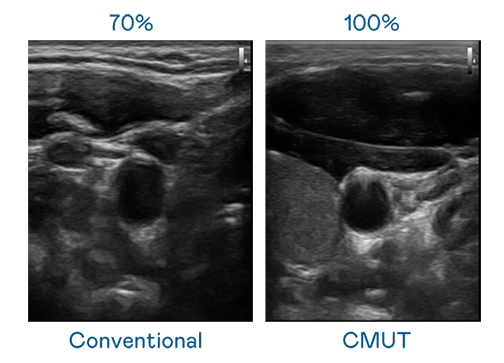

CMUT 技术是一种用电容式微机电元件来产生超音波讯号的技术。与传统 PZT 压电式技术相比,CMUT 频宽增加 30%,更宽频的超音波讯号让影像解析度大幅提升,是实现高影像品质医疗超音波扫描、促进精准医疗发展的关键技术。

超音波影像的解析度高低,首先取决于探头能发出的讯号频宽。币赢 CMUT 可提供高清晰的超音波讯号,提供高频宽、高灵敏度、影像纹理细节更高的超音波影像,协助医护人员缩短影像判读时间及利用精准的医疗影像进行诊断。